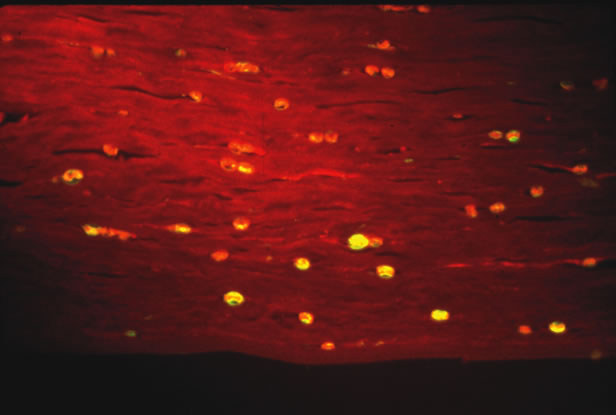

Some parasites can be seen free living under the microscope. Onchocerca volvulus, the causative agent of river blindness, can be directly observed swimming out of skin or corneal biopsies incubated in saline or culture medium. Modern imaging techniques are increasing the range of organisms that can be directly detected in situ. In particular, the confocal microscope has been successfully used to visualize Acanthamoeba in infected corneas.2 Certain parasites causing ophthalmic disease can be visualized with special stains. Acanthamoeba species can be visualized on corneal scrapings with PAS or GMS stains, or with the fluorescent dyes calcifluor white or acridine orange (Fig. 3). Both techniques require a fluorescent microscope to visualize the dye. Calcifluor white (a whitening agent used in laundry detergents) stains Acanthamoeba cell walls and fluoresces green under ultraviolet illumination. Toxoplasma gondii can be visualized with PAS or GMS stains from biopsy material. Specific antisera can be used in stains of biopsy specimens.

Fig. 3. Acanthamoeba in cornea stained with calcifluor white and imaged with ultraviolet fluorescence microscopy. (Photomicrograph courtesy of Dr. Morton Smith.)